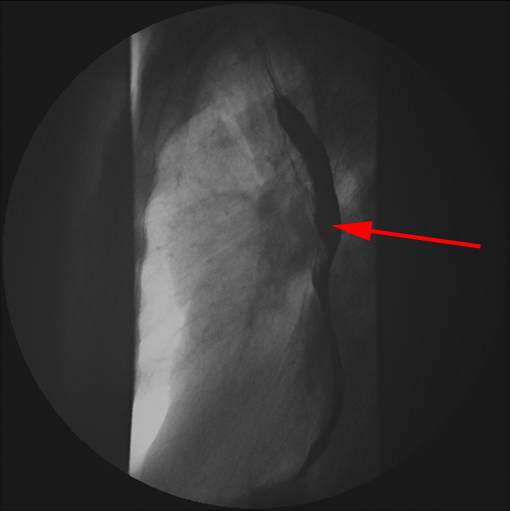

Nederste del af øsofagus med kontrast optaget forfra og fra siden (nederste billede)